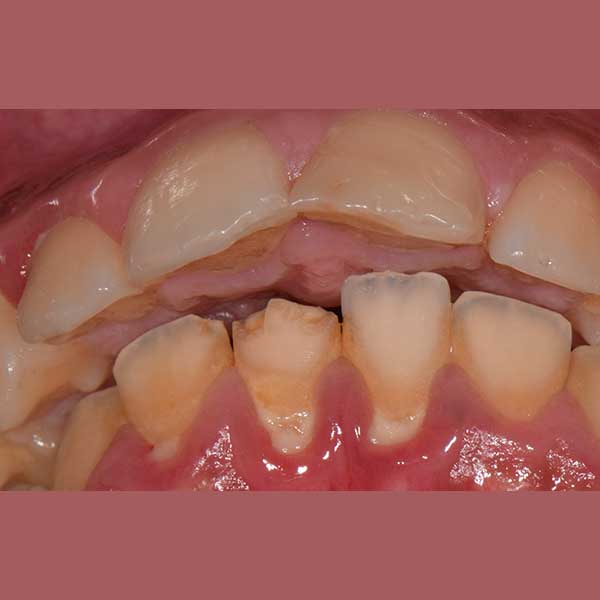

BEFORE

This little kid was suffering from severe protrusion (there was a space between the upper and lower front teeth), and regression in the lower jaw.

The condition was treated by fixed orthodontics and a functional device that serves to advance the lower teeth and the bearing bone forward and stimulate the advancement of the lower jaw forward and Put the upper teeth back.

The case was successfully treated without tooth extraction, as is usual in some similar cases.